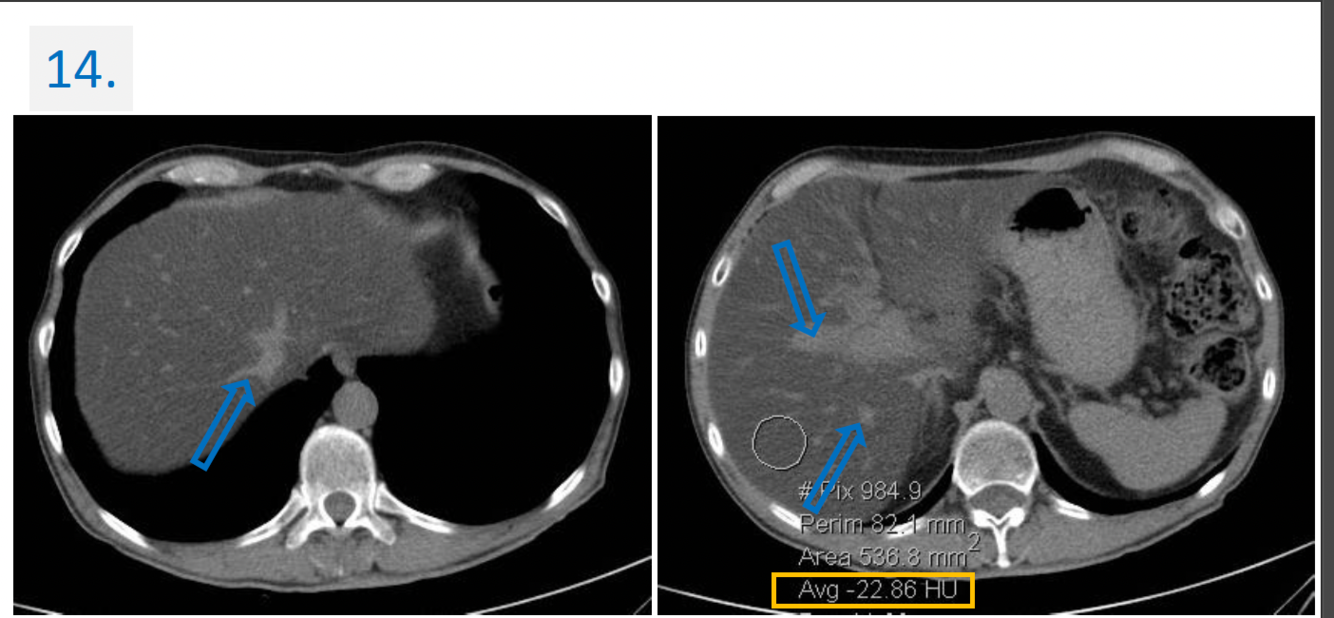

14.

Modality:

Noncontrast CT

Region:

Upper abdomen, axial views

Radiologic sign:

-Diffusely & homogenously decreased density (cca. -20 HU) of the liver

(normal density is cca. 50-60 HU).

-The vessels (blue arrows) → denser -relative to the liver parenchyma-

Diagnosis:

Steatosis Hepatis (Fatty liver)